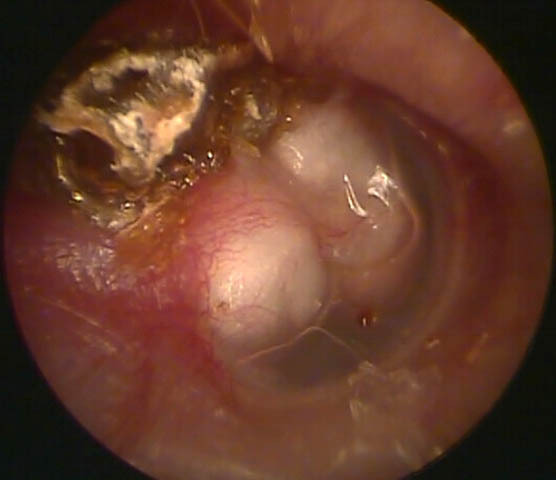

Question 9 - Que pouvez-vous dire du tympan (une ou plusieurs réponses exactes) ?

C’est une otite chronique avec inflammation du tympan.

C’est la grosse masse blanchâtre derrière le tympan.

C’est une otite chronique avec un cholestéatome : il a donc une inflammation.

On voit le tympan dans la partie inférieure, ce n’est pas une perforation du tympan.

Rappel sur ce qu’est un cholestéatome. Il y a normalement à l’intérieur de la caisse du tympan uniquement de la muqueuse. Lorsqu’une poche de rétraction du tympan (donc une poche qui est aspirée dans la caisse) se perce, on se retrouve avec de la peau à l’intérieur de la caisse. Cette peau s’accumule et par une réaction chimique locale (ce n’est pas une invasion tumorale) entraîne une lyse progressive de contact des structures osseuses.

Vous diagnostiquez donc un cholestéatome de l’oreille droite.